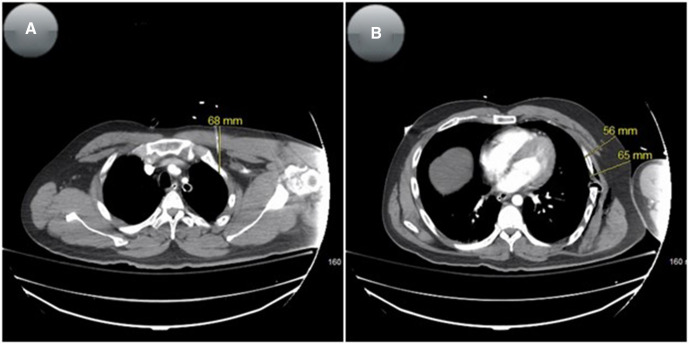

제시된 근거에 따르면, 본 연구는 모든 진료 환경에서 의심되는 TPT에 대해 NT 시 긴 안지오카테터를 사용할 것을 지지한다. 병원 전 구급대원들은 84명 중 81명(96%)에서 NT 삽입 부위로 2번 ICS-MCL을 선택했다. 그러나 이 부위에서 환자의 63%가 CWT 50㎜ 이상(그림 2 참고)이었으며, 짧은 5㎝ 안지오카테터로는 효과적이지 않았다. 또한 약 20%의 환자들은 CWT가 70㎜ 이상이었는데, 이는 긴 8.25㎝ 카테터를 사용하더라도 여전히 오차의 여지가 거의 없음을 의미한다. CT 소견에 근거할 때 NT가 흉막강에 적절히 삽입된 경우는 단 23명(27.4%)에 불과했다. 적절 삽입과 부적절 삽입 간 사망률 차이는 통계적으로 유의하지 않았으나(91.3% vs. 82.0%, p=0.4994), 적절 삽입군이 퇴원 시 생존 가능성과 더 높은 연관성을 보였으며, 이는 외상성 TPT가 의심되는 환자에서 NT의 정확한 시행이 얼마나 중요한지를 다시금 강조한다.